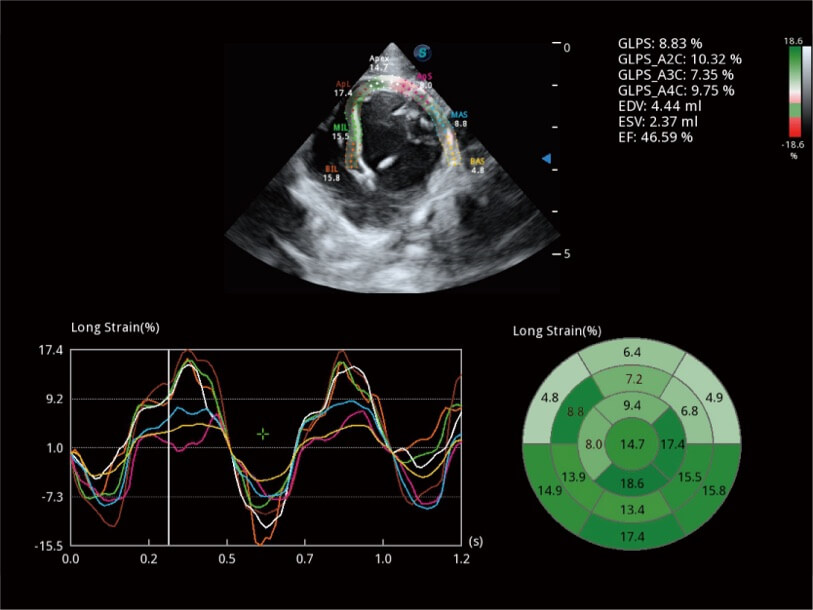

Die präzise Erkennung der linksventrikulären Wandbewegung mit globalem 2D-Speckle-Muster-Tracking ermöglicht eine genaue quantitative Analyse einschließlich Dehnung, Dehnungsrate, Auslenkung, Geschwindigkeit usw. der Myokardwände.

Erfasst Daten mit bis zu 3 Messlinien auf einmal, um die Wandbewegung detailliert beurteilen zu können. Verbessert die Reproduzierbarkeit und Genauigkeit der linksventrikulären Messwerte erheblich.